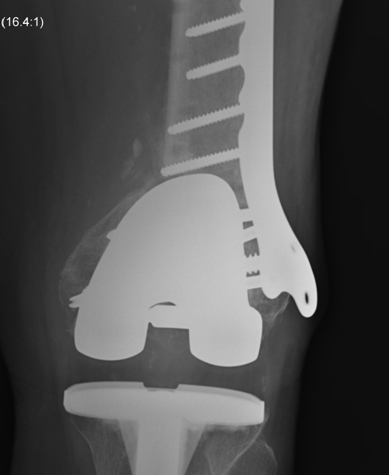

4.  Revision TKR

Indications

- very distal fracture

- insufficient bone stock

- loose prosthesis

Components

- stemmed, constrained implant

- tumour prosthesis

Periprosthetic TKR Tibial Fracture 1Periprosthetic TKR Tibial Fracture 2Periprosthetic TKR Tibial Fracture 3Periprosthetic TKR Tibial Fracture 4

TKR Periprosthetic Fracture APTKR Periprosthetic Fracture LateralTKR Periprosthetic Fracture Revision APTKR Periprosthetic Fracture Revision Lateral